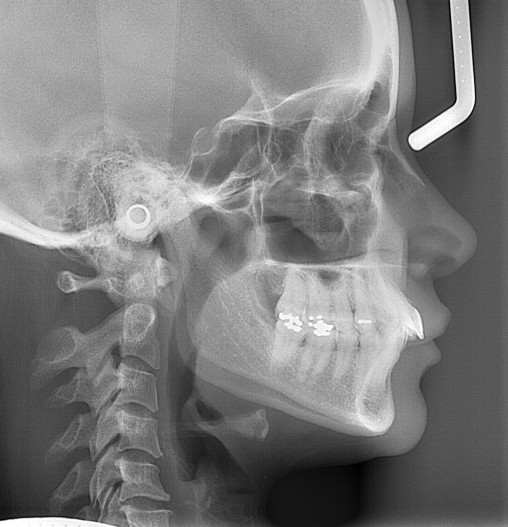

Sehr häufig gehen anteriore Tiefbisse mit einer Klasse II-Okklusion einher. So auch bei dieser 47-jährigen Patientin, bei der die starke Verschlüsselung der Okklusion zu einer Kompression beider Kiefergelenke und funktionellen Beschwerden geführt hat. Sie stellte sich bei uns in der kieferorthopädischen Praxis mit Nackenbeschwerden, Kopfschmerzen sowie reziprokem Kiefergelenkknacken rechtsseitig vor. Ihr Hauptanliegen war daher eine funktionelle Verbesserung, sie wünschte sich aber auch eine ästhetische Zahnkorrektur mittels Alignerbehandlung. Die Patientin störte sich ästhetisch vor allem an den aufgefächerten Oberkieferfrontzähnen. Eine kieferorthopädische Behandlung war bereits im Jugendalter erfolgt. Die Funktionsanalyse ergab eine Diskusdislokation rechtsseitig bei Kompression beider Kiefergelenke. Die Mundöffnung war eingeschränkt und erfolgte wie der Mundschluss mit Deviation. Der extraorale Befund (Abb. 1a–c) zeigte ein konvexes Gesichtsprofil bei deutlich verkleinertem Nasolabialwinkel (90,8°). Zudem waren Impressionen der Oberkieferzähne in der Unterlippe erkennbar.

Die FRS-Auswertung (Abb. 1d) ergab eine distal-basale Kieferrelation nach WITS (2,6 mm) bei tendenzieller maxillärer Prognathie (SNA 86,5°). Aus der dentalen Analyse des FRS ging eine deutliche Anteinklination der Oberkieferinzisivi (IOK-NL 126,5°) und eine manifeste Anteinklination der Unterkieferinzisivi (IUK-ML 103,6°) bei stark verkleinertem Interinzisalwinkel (IOK-IUK 112,3°) hervor. Die vertikalen Parameter ergaben einen brachiofazialen Gesichtsschädelaufbau. Die Auswertung des OPG (Abb. 1e) zeigte eine adulte Dentition mit fehlenden dritten Molaren. Außerdem war eine extreme Mesialkrümmung der Wurzel 25 erkennbar. Es zeigte sich ein moderater generalisierter horizontaler Knochenabbau des Limbus alveolaris im Ober- und Unterkiefer von ca. 15 Prozent.